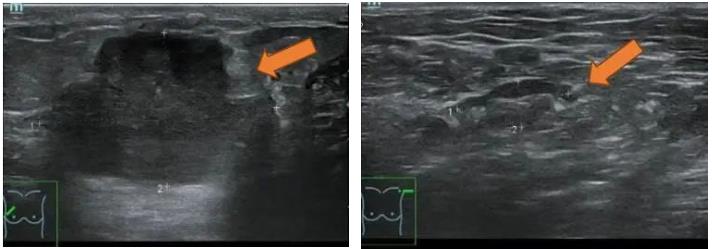

2021.6.28乳腺超声示:右乳外上象限实性肿块,考虑乳腺癌(BI-RADS-5类)。

右乳10点方向腺体层探及一实质低回声肿块,大小约35.1×22.6mm,内部回声不均匀,其内可探及多个点状强回声,边界不清,形态不规则,周边可见毛刺征,CDFI、CDE示其内血供丰富。右侧腋窝探及多个实质低回声结节,大者约10.2×5.2mm,皮质稍增宽,CDFI、CDE示其内血供不丰富。

图1. 乳腺超声

(2 cycle 后)2021.8.31 乳腺超声示:右乳10点实性肿块 44.9mm×13.1mm。

图5. 乳腺超声